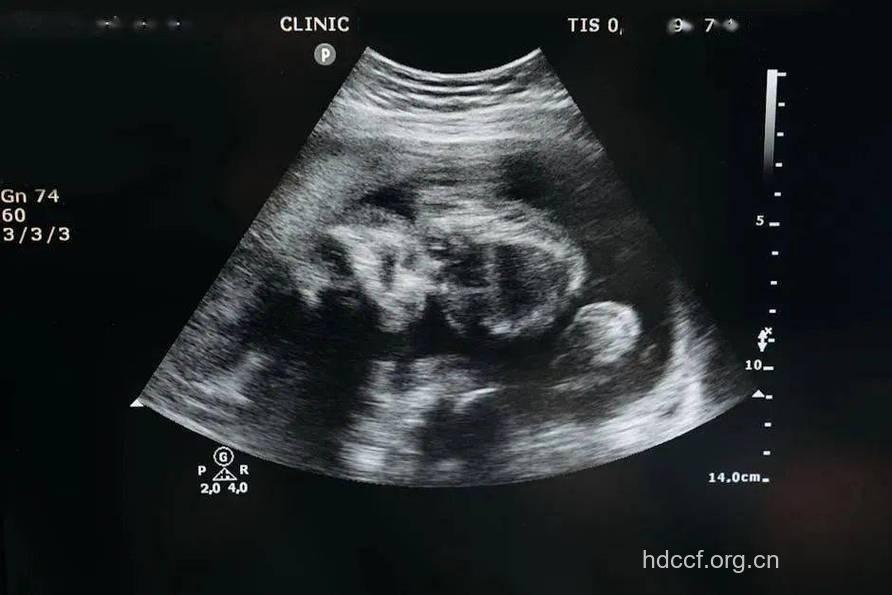

B超,学术名称为B型超声波诊断,是一种无损伤无痛苦的检测方法。它可以显示人体实质脏器的疾患,对于胎儿的情况也可以清楚地显示出来。

B超检测胎儿是否畸形有很多优点:可直接观察脏器的状态;对人体无创伤、无痛苦;可以帮助胎盘定位;能清晰显示人体软组织的解剖结构;简便、准确等。

通过B超检查还可以依次对胎儿的头部、颈部、胸部、腹部进行扫查,可诊断连体畸形、小头畸形等。高分辨率的B超甚至可对唇裂等微小畸形准确诊断。对于高度怀疑畸形胎儿,也可用B超进行诊断,如无脑儿可在妊娠三个月后检出;脑积水,神经管畸形中的脑脊膜膨出,脐带异常,消化道异常等也能检出。